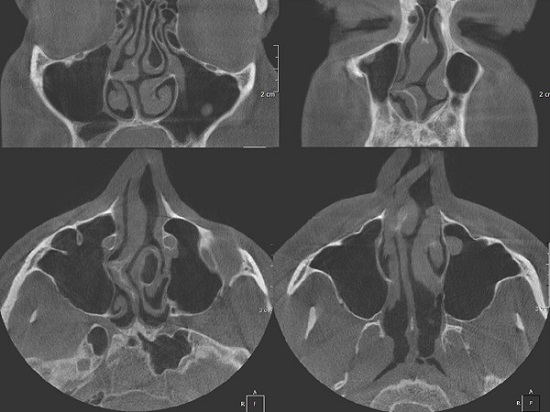

Например, искривление носовой перегородки может привести к «неправильному дыханию». В результате холодный воздух не успевает прогреваться, а содержащиеся в нём микроорганизмы не фильтруются защитными механизмами организма.